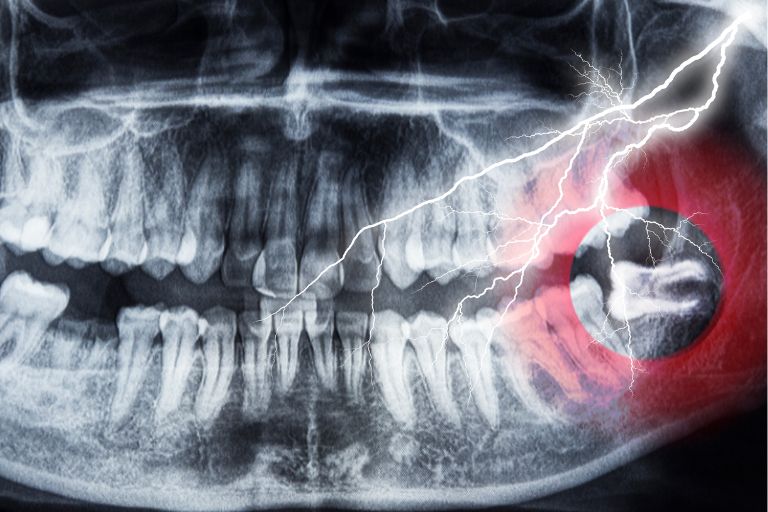

親知らずの抜歯でCTが必要になりやすいケース

CTスキャンで立体的に構造を確認することで、安全性を考えた抜歯計画を立てやすくなります。

例えば親知らずが神経に近い深い位置にある、埋まっているなどの場合は、通常のレントゲンだけでは判断材料が足りずCTスキャンが必要になることがあります。

下顎の親知らずが下歯槽神経に近い

下顎の親知らずが感覚を担う神経「下歯槽神経」に近い位置にあると、抜歯時に神経損傷のリスクも考えられます。

そのため、CTスキャンで神経などの位置関係を確認して手術計画を立てます。

CTスキャンは痛みの軽減につながることも

CTスキャンは親知らずの向きや根の形状を詳しく把握できるため、事前に難易度を確認して手術計画を立てられるのがメリットです。

結果として、手術時間の短縮や腫れ、出血、痛みなどの軽減につながる場合があります。

例えば親知らずが真っすぐ深く埋まっていて器具が届きにくい場合などは手術が難しいことがあります。抜歯の難易度は角度・位置・骨や神経との距離などで変わり、CTスキャンやパノラマレントゲンで確認した上で、手術計画を組みます。